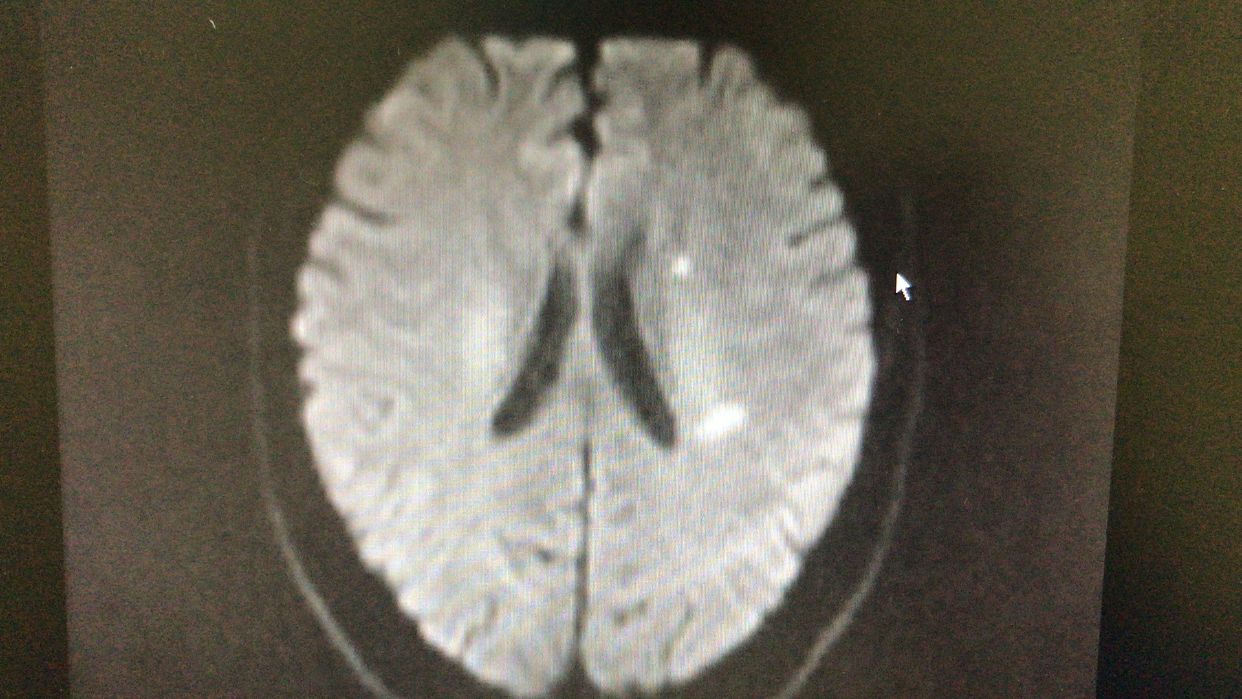

男性,70岁,头晕伴右侧肢体无力及言语不利4小时入院,入院后头颅CT排除脑出血,随行头颅核磁共振检查!

右侧大脑半球散在梗塞!